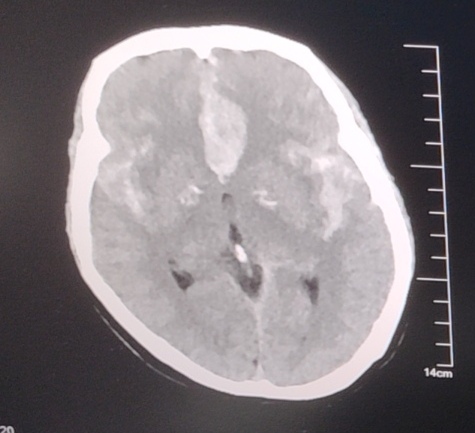

头颅CT情况:SAH

患者女性,突发起病,外院CT提示SAH,前纵裂血肿。

双侧颈内造影

3D重建情况